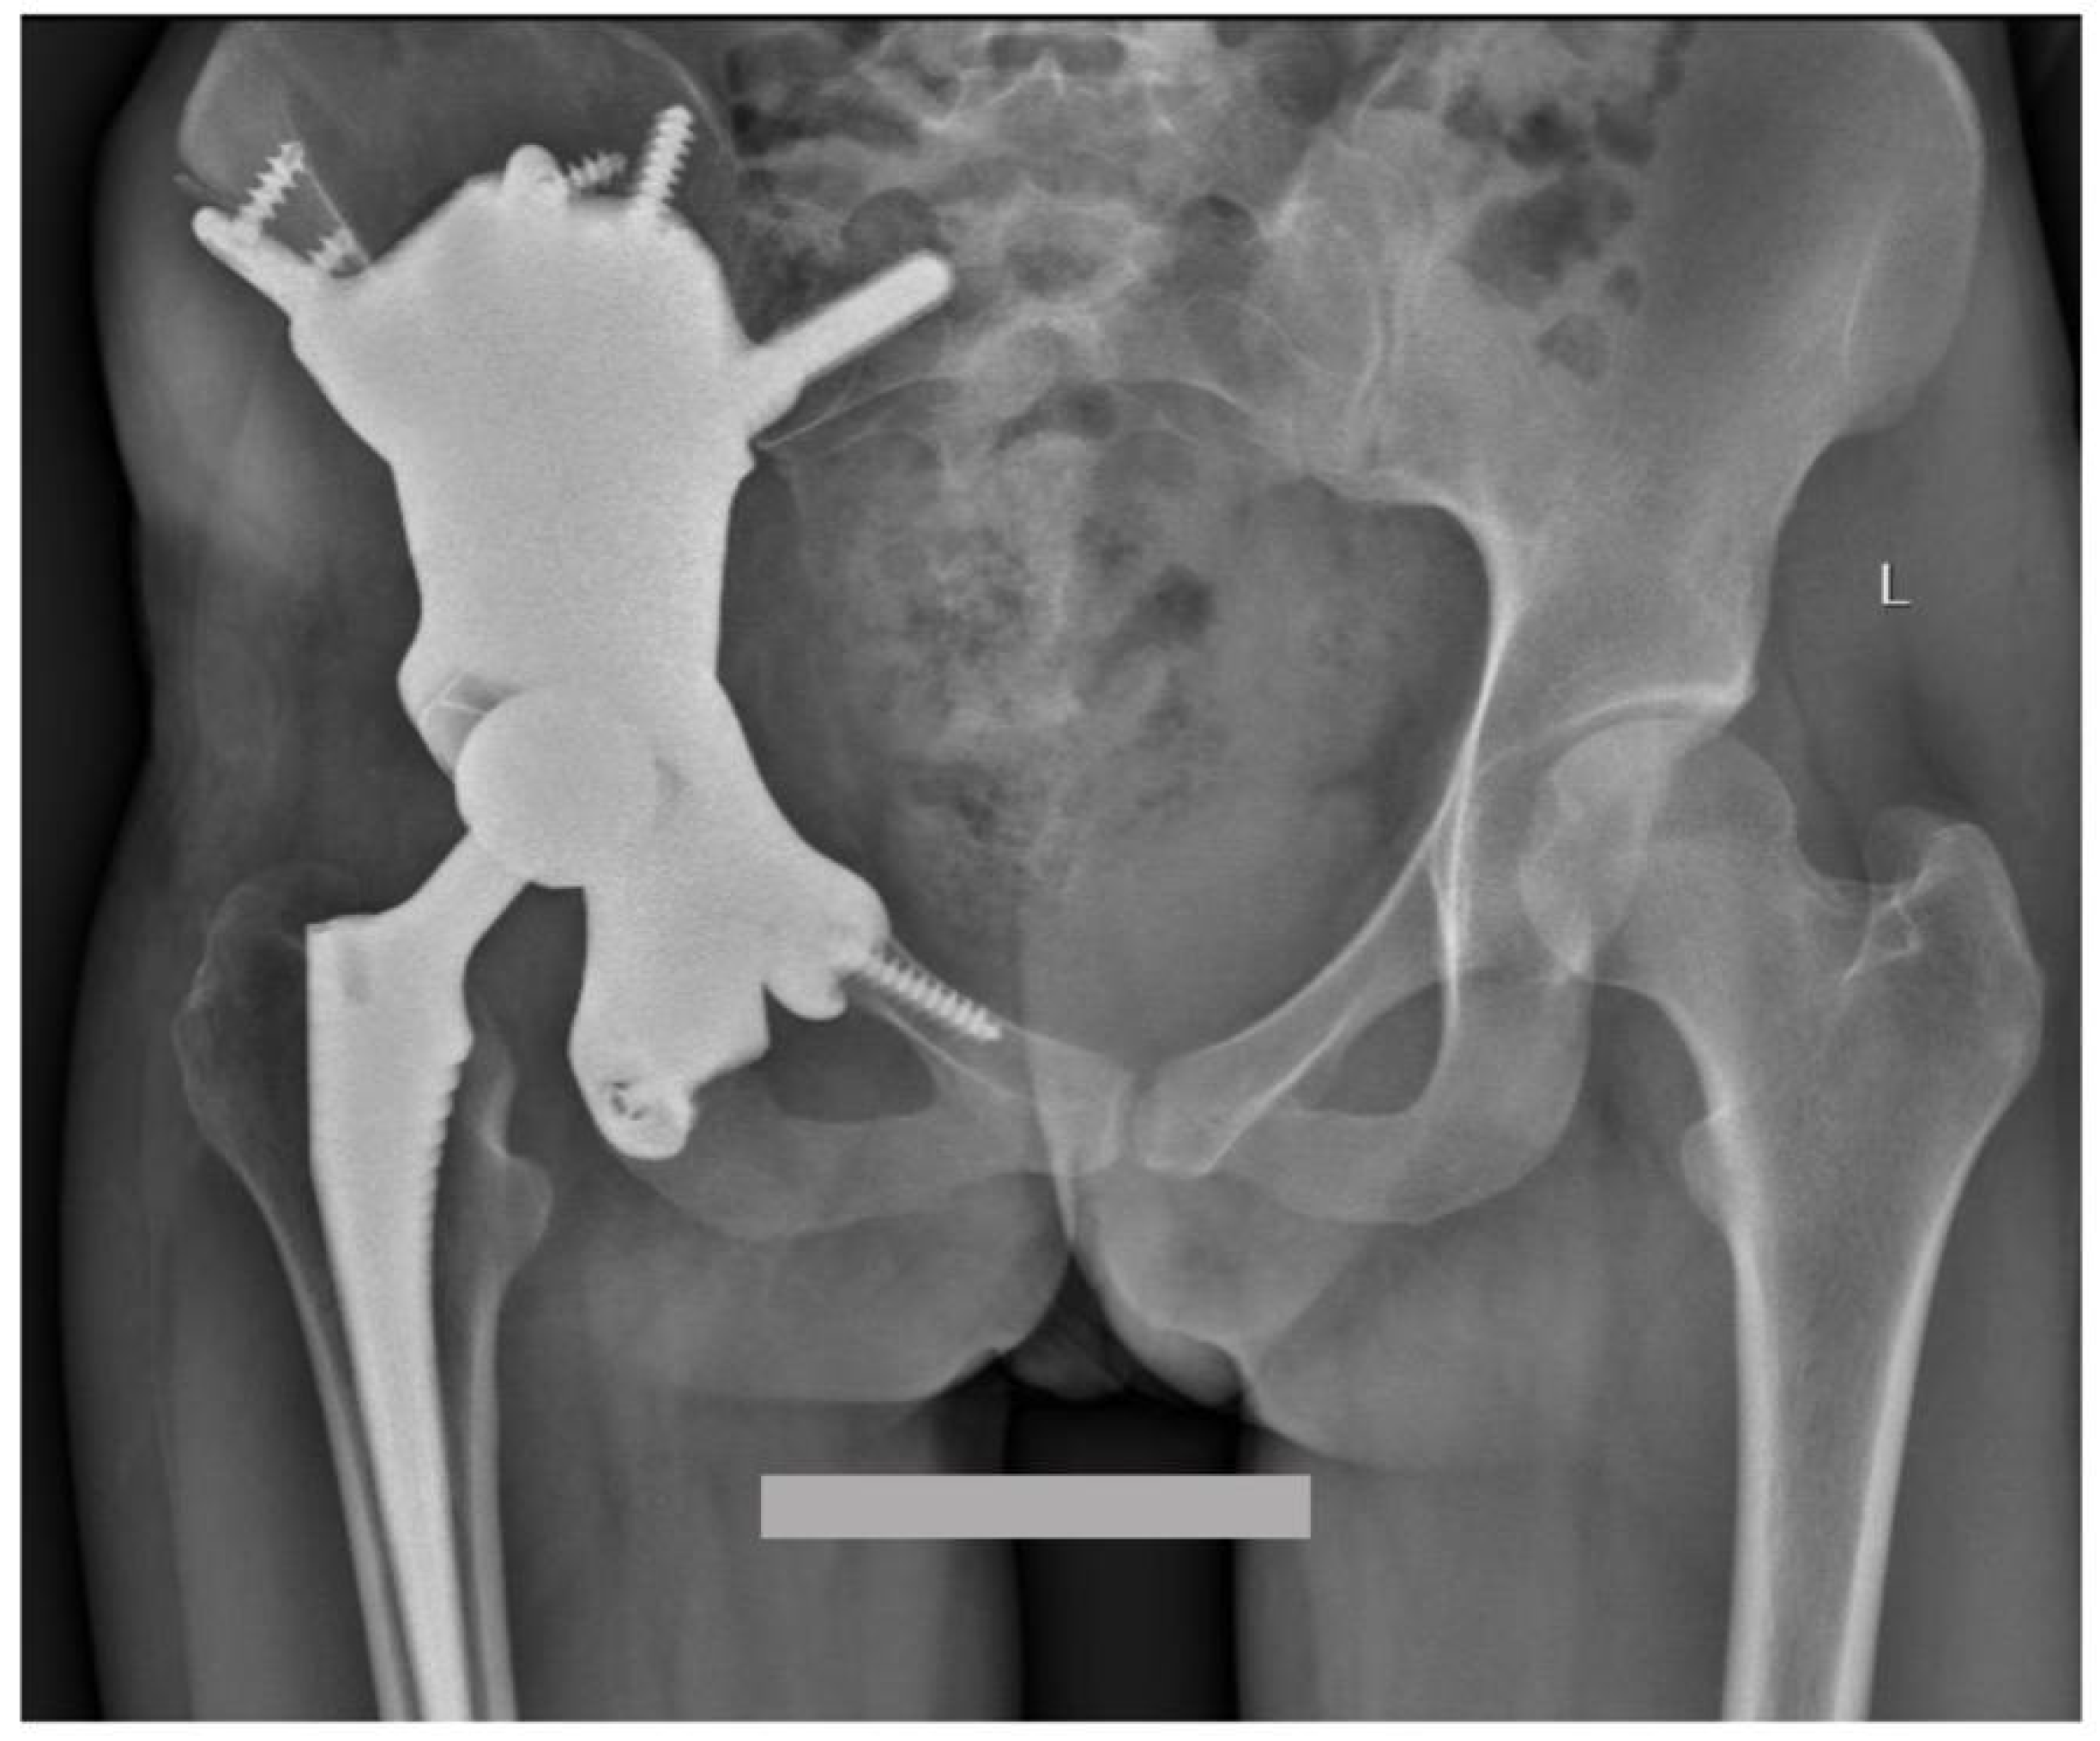

Custom-Made 3D-Printed Prosthesis after Resection of a Voluminous Giant Cell Tumour Recurrence in Pelvis

2. Case Presentation